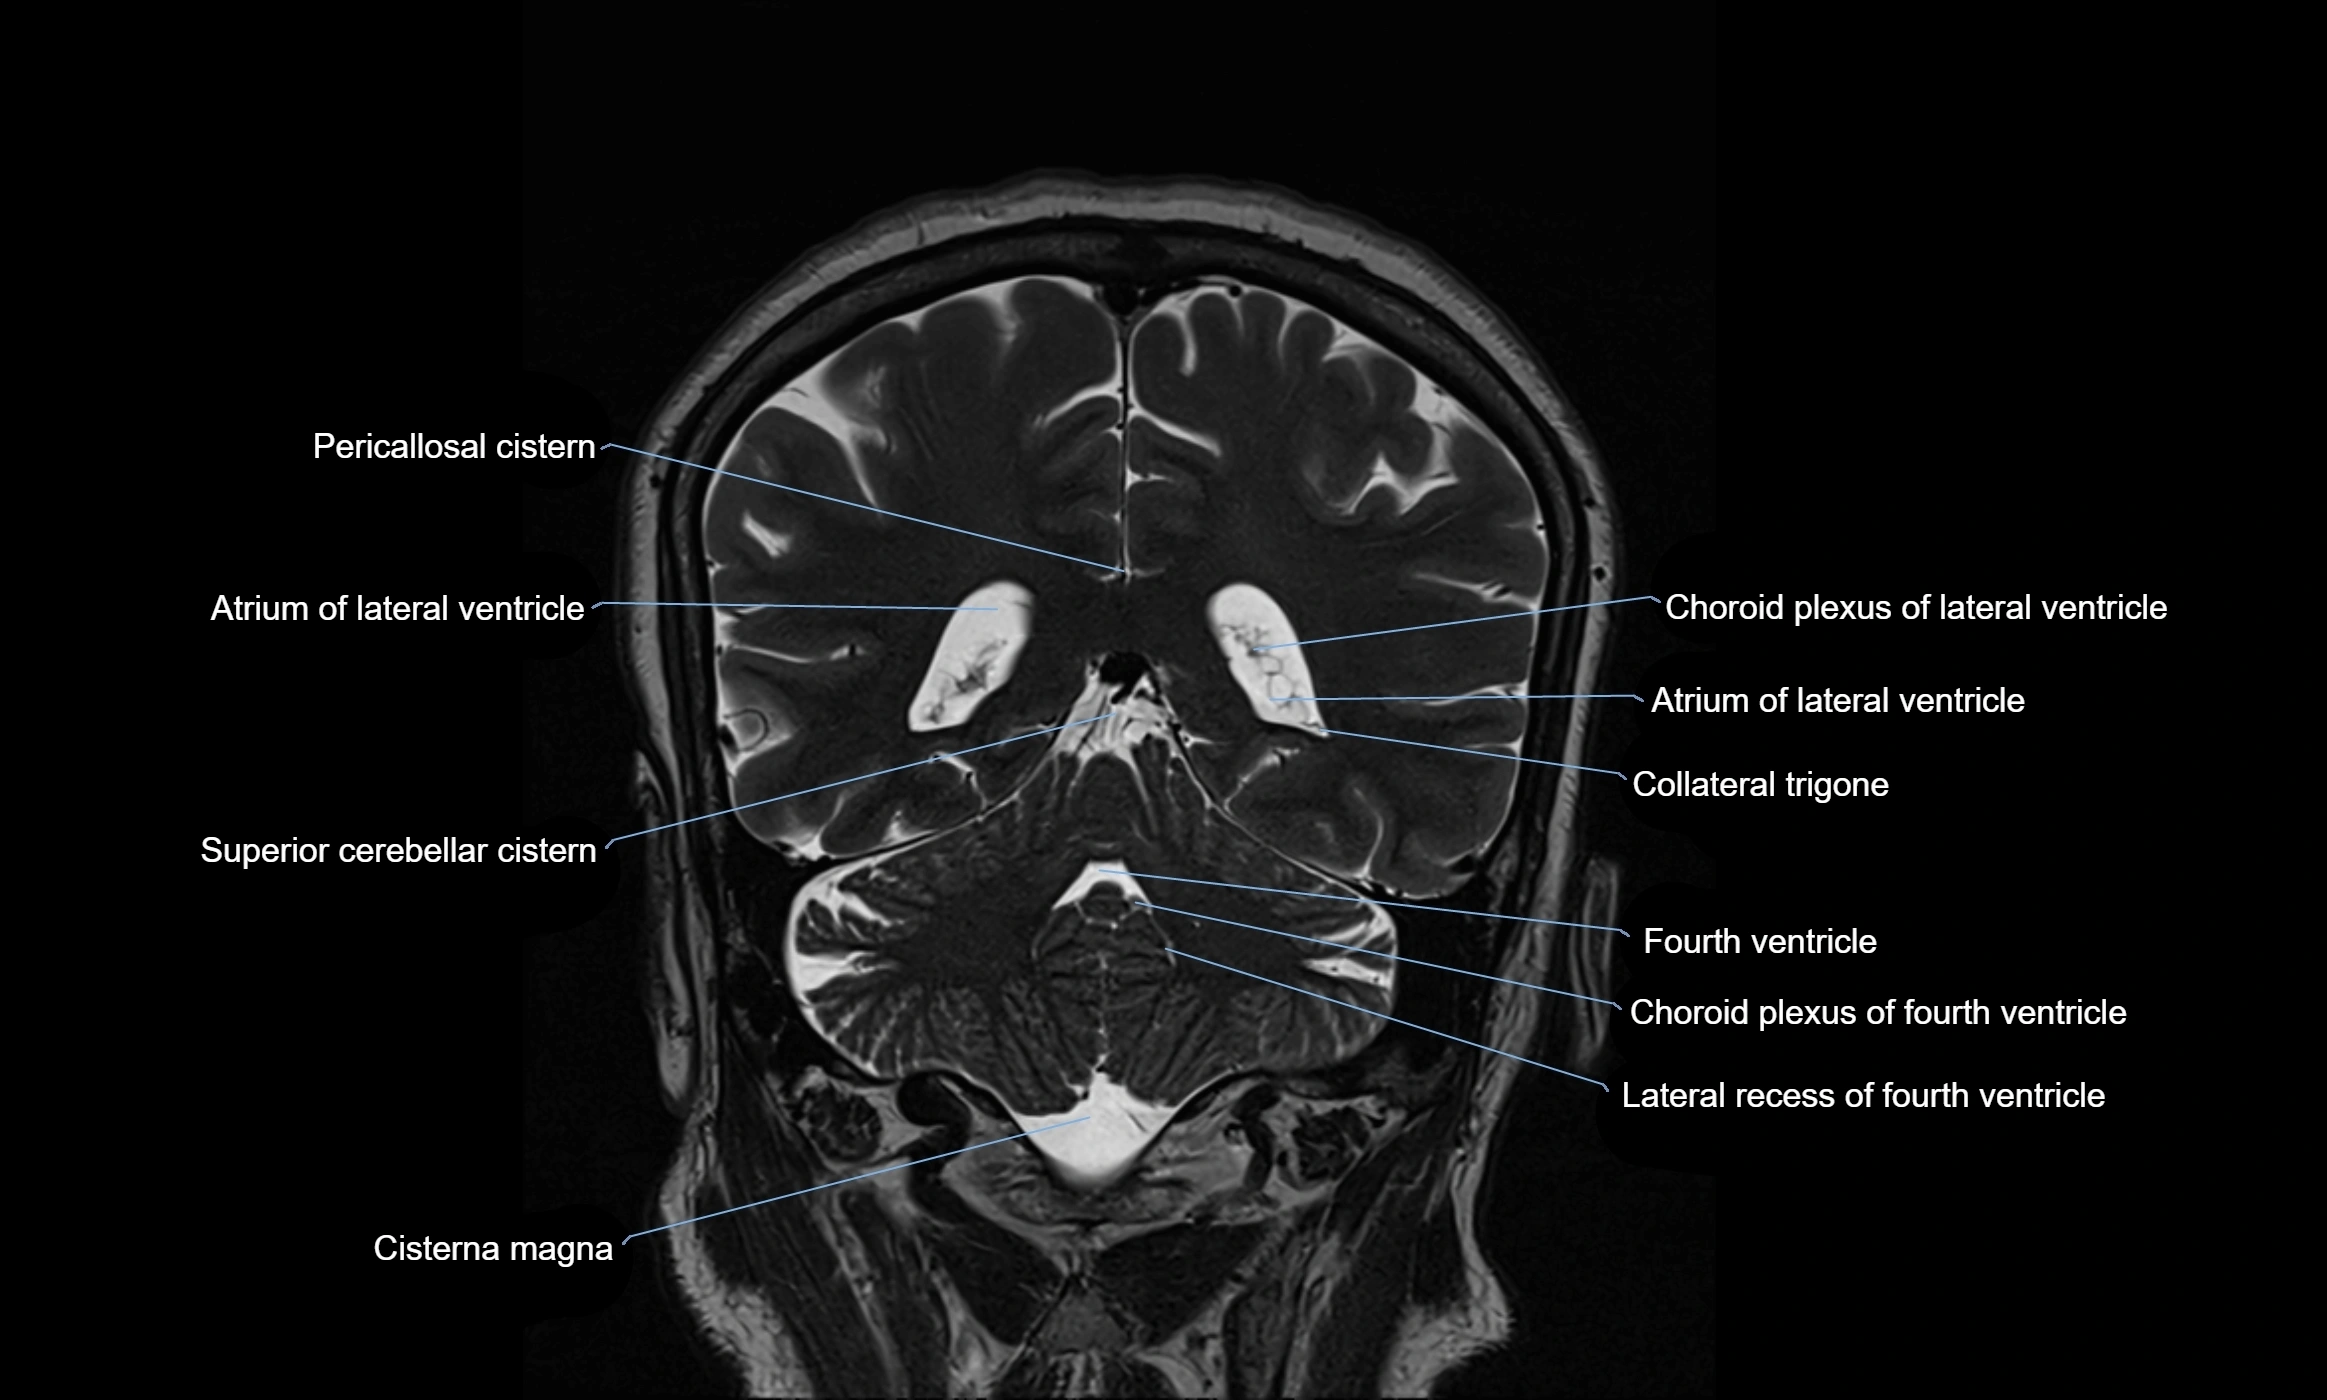

MRI images

image